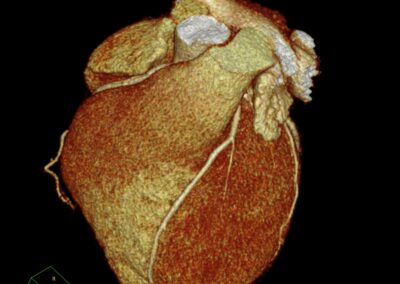

Τρισδιάστατη και δισδιάστατη απεικόνιση των στεφανιαίων αγγείων όπου διακρίνεται σημαντική στένωση λίγο μετά την έκφυσή του πρόσθιου κατιόντα κλάδου